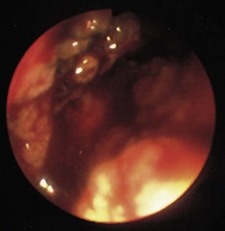

Abnormal findings: Proctoscopic examination of the anus and lower rectum can confirm or exclude the presence of haemorrhoids, anal fissures and rectal prolapse. Rectal mucosa looks like buccal mucosa, apart from the presence of prominent submucosal veins. During straining, haemorrhoids distend with blood and may prolapse. If the degree of protrusion is more than 3–4 cm, a rectal prolapse may be present.